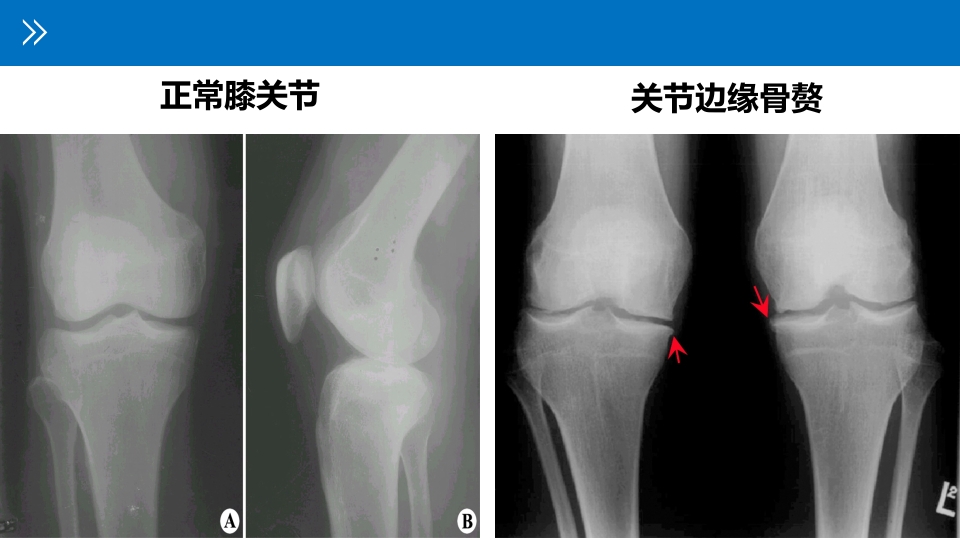

退行性膝关节病变 ——骨性关节病、增生性关节炎、变形性关节病、老年性关节炎 Xxx医院:xxx 退行性膝关节炎 degenerative arthritis 退行性膝关节炎:是由于膝关节的退 行性改变和慢性积累性损伤,以膝 部关节软骨变性,关节软骨面反应 性增生,骨刺形成为主要病理表现, 以膝关节疼痛、运动受限为主要临 床症状的一种病症。 01 05 目录 02 06 CONTENTS 03 07 04 08 解剖生理: 1 膝关节的解剖 由一层光滑关节软骨覆盖的 关节面与外层为纤维膜,内层 为滑膜的关节,以及含少量滑 液密闭腔隙的关节腔组成; 三个辅助结构: ①关节盘:由外侧“O”型半月 板和内侧“C”型半月板构成; ②关节唇:附于关节窝周缘的纤 维软骨环; ③韧带:分为囊内韧带(前后交叉 韧带)、囊外韧带(腓侧副...